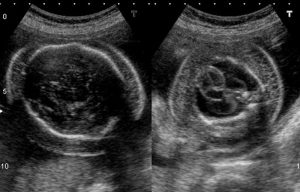

Khi siêu âm thấy thai có phù da kèm theo tràn dịch một hoặc nhiều khoang, bác sĩ sẽ nghĩ đến phù thai và cần đánh giá nguyên nhân ngay. Phù thai không phải là hiện tượng sinh lý bình thường trong thai kỳ.

Phù thai chủ yếu được phát hiện qua siêu âm thai. Các dấu hiệu gợi ý bao gồm:

- Da thai dày bất thường

- Dịch quanh tim, quanh phổi hoặc trong ổ bụng

- Đa ối

- Bánh nhau dày